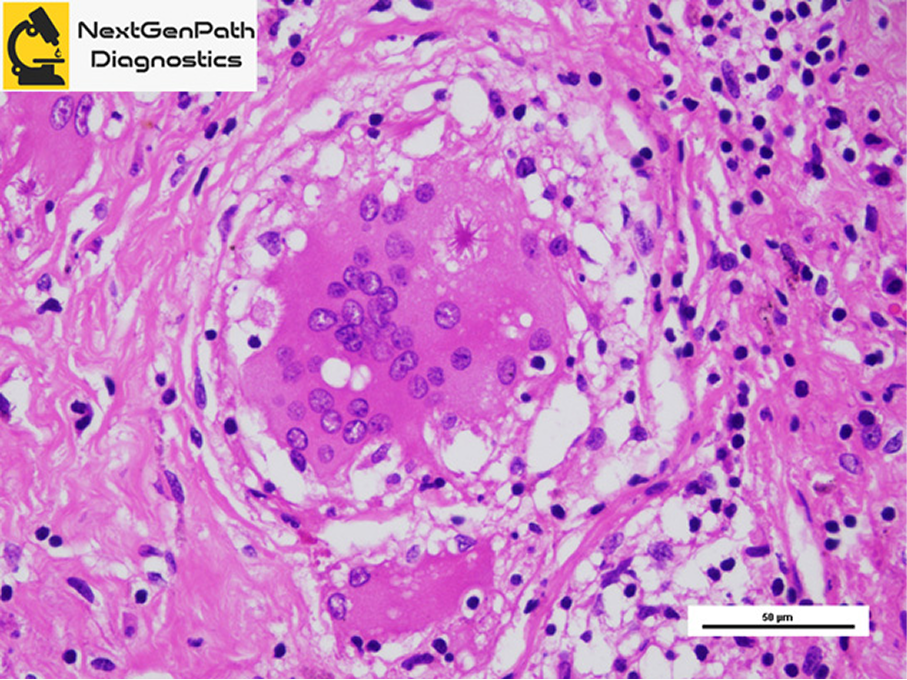

Ophthalmic Pathology

- NextGenPath Diagnostics handles a broad range of biopsies and resections of eye and orbit.

- Ophthalmic pathology is a rare subspecialty of Histopathology, which needs interpretation by an expert ophthalmic pathologist .